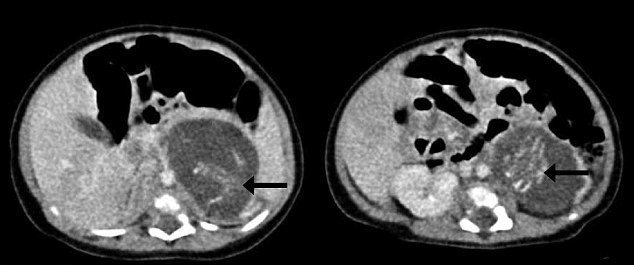

Стрелками показаны зачатки позвоночника плода. © hkmj.org

Когда новорожденной исполнилось три недели, ей сделали операцию, в ходе которой было удалено два плода весом 9,3 и 14,2 грамма и длиной в 35 и 37 миллиметров. Это примерно соответствует 10-недельной беременности. Оба плода имели пуповину, конечности, кожу, ткани мозга, грудную клетку, зачатки позвоночника и другие части тела.